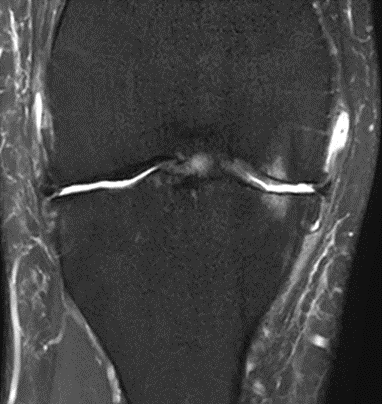

MRI scans illustrating the improvements regarding Group 2 are presented below, showing pre-treatment images with evident cartilage defects, pronounced bone marrow edema, and synovial inflammation, followed by post-treatment scans demonstrating improved joint structure, reduced edema, and decreased inflammation (Figures 12-29).

MRIs of Group 1

To provide a comparative perspective, additional MRI scans from Group 1 are shown subsequently. While patients in this group also displayed reductions in bone marrow edema, effusion, and synovitis, the improvements appeared less pronounced than those seen with the combined therapy. Pre-treatment MRI scans revealed extensive edema and synovial inflammation, which were partially reduced at the 2-month follow-up. However, residual joint effusion and subtle signs of inflammation remained present in some cases. These findings further support the potential benefit of combining the ChondroFiller® liquid with MSC therapy to achieve more comprehensive structural improvements and facilitate enhanced cartilage regeneration (Figures 30-41).

Figure 32: Male, 71 years, pre-intervention MRI.

Figure 33: Male of figure 32, two-month follow-up MRI: MSC only. only.